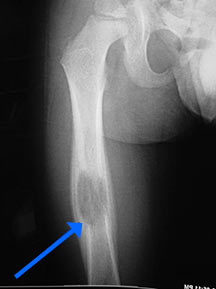

- May arise from any bone and any site within a bone (epiphyseal, metaphyseal, diaphyseal)

- Radiographically variable appearance: may appear benign (geographic) or malignant (permeative or moth eaten)

Sites:

- Flat Bones (most common—70%)

- Skull

- Pelvis

- Femur

- Humerus